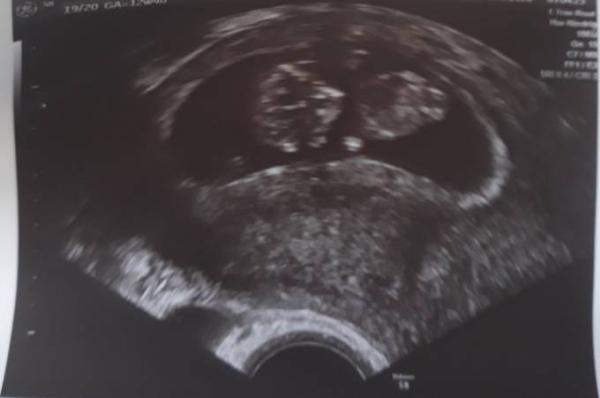

Ohhhh wie toll und ein schönes Bild hast du da ich habe ganz feste an dich gedacht und freue mich sehr für dich das alles gut ist Ich würde den Termin an deiner Stelle einfach verschieben dann hast du nochmal einen US in ein paar Tagen Ich war auch eben beim FA und bin überglücklich. Mein Baby sieht einfach aus wie ein kleines Gummibärchen ich bin soooo verliebt

Bild zu